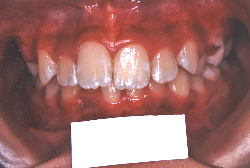

成長発育期の叢生症例・非抜歯治療

今回は「歯並びの凸凹を治したい」という主訴で来院したケースです。診断の結果、「成長発育期の叢生」と判明しました。叢生とは歯並びの凸凹のことですが、この方の場合は上顎が少々重症で、上の犬歯が外側へ飛び出し、いわゆる「八重歯」という状態でした。凸凹の解消のためには永久歯を抜歯して隙間を作って残った歯をきれいに配列する方法(抜歯法)と、歯列を拡大して配列する方法(非抜歯法)の2種類があります。歯列の拡大にはさらに2つの方法が有り、横方向へ拡大する場合と、臼歯を後方に移動させて拡大する方法があります。今回の症例のようなケースでは、横方向へ拡大してもあまり効果的ではなく、後方への移動が最適です。上の臼歯を後方へ移動させるために、今回はヘッドギヤという取り外し式の装置を、夜寝る時に半年ほど使用していただきました。

注意点としてここでお伝えしたいのは、矯正専門医ではない歯科医院で、いわゆる「床矯正」という方法を行うと、たいてい横方向の拡大になってしまいます。無駄に横方向の拡大をするとかえって症状を悪化させたり、何の効果もないことになってしまいます。一見簡単そうな矯正に見えたとしても、しかるべき矯正専門医に診断してもらうことをおすすめします。

この方の場合、治療期間はヘッドギアを6ヶ月、マルチブラケット法を7ヶ月でした。治療後は凸凹が改善しただけでなく唇の審美性が大幅に改善しました。もちろん噛み合わせ的にも正しい状態が確立しています。